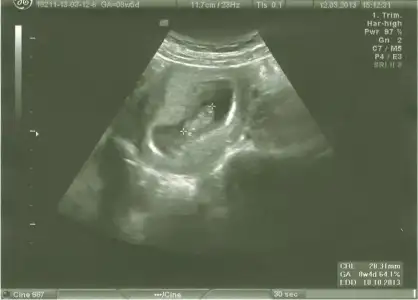

dr soylemeden siz gorun genital nub teorisi ( bebegin cinsiyeti)

gozum kaydı buraya "bı bakayım" dedım "aaaaaaaa! bızım kızın 11+4te paralelmıs":)))

teoriye göre bakınca paralelse kız dikse erkek diyoruz ama ben bacaktan hiç ayırd edemiyorum bu nubu yahu...